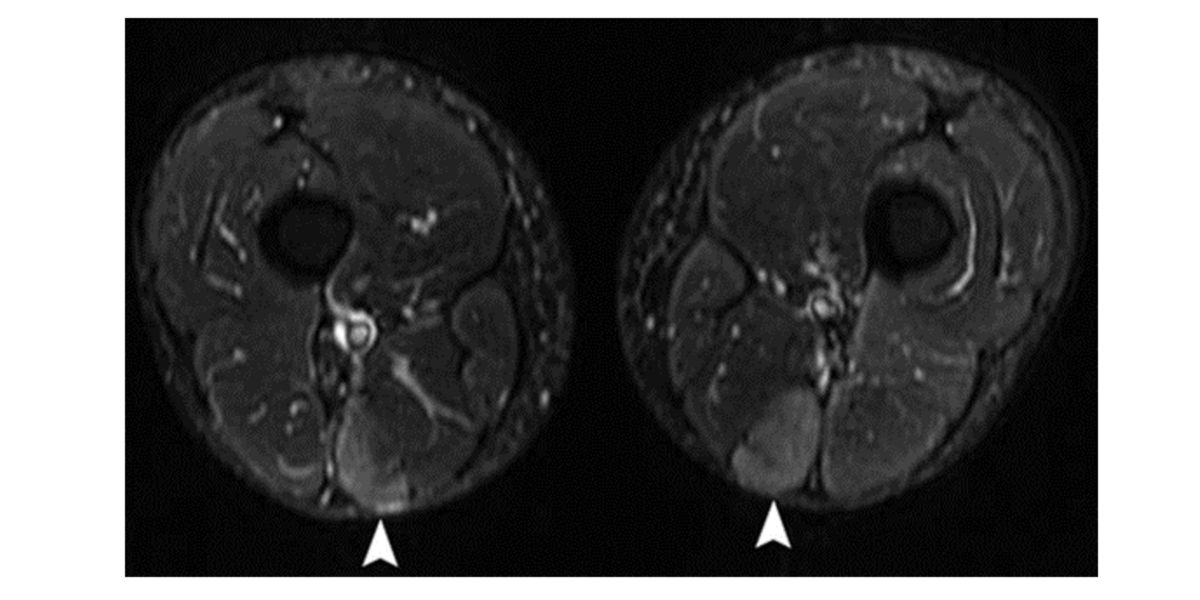

Non solo questo, ma anche un eccessivo danno muscolare che provoca la morte cellulare e l’edema interstiziale: guadagnare peso perché si accumula una quantità anomala di acqua intorno alle cellule come meccanismo di protezione dopo un allenamento eccessivo.

Figura III. Immagine di una risonanza magnetica in cui si osserva edema (freccia) nel muscolo semimembranoso dopo aver corso una maratona (McMahon et al., 2010).